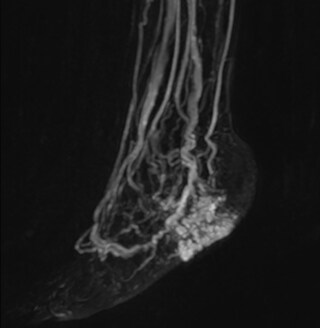

The subtractionless peripheral MR angiography shows improved vessel-to-background contrast and high resolution. Ingenia Ambition 1.5T.

Another example is the foot examination for diabetic patients, which has improved dramatically. “The forefoot is generally difficult to image with MRI because of the inhomogeneities that the toes create – it’s hard to obtain good fat saturation in that area. Here, mDIXON made a huge difference right away, we obtain much better image quality,” Dr. Peña says. “Using mDIXON, Compressed SENSE and the dS FootAnkle coil, we have been able to reduce the scan time, so that we can now also include an additional 3D STIR sequence to visualize both arteries and veins in the foot.”

Avila adds: “In addition, since most of these patients are in a significant amount of pain, it’s important to perform the examination as quickly as possible. With Compressed SENSE and mDIXON we have been able to reduce the scan time from about 45 minutes to just 15 minutes. Not only does this improve patient comfort, we see that it also helps us acquire images without motion artifacts, which is critical to making a confident diagnosis.”